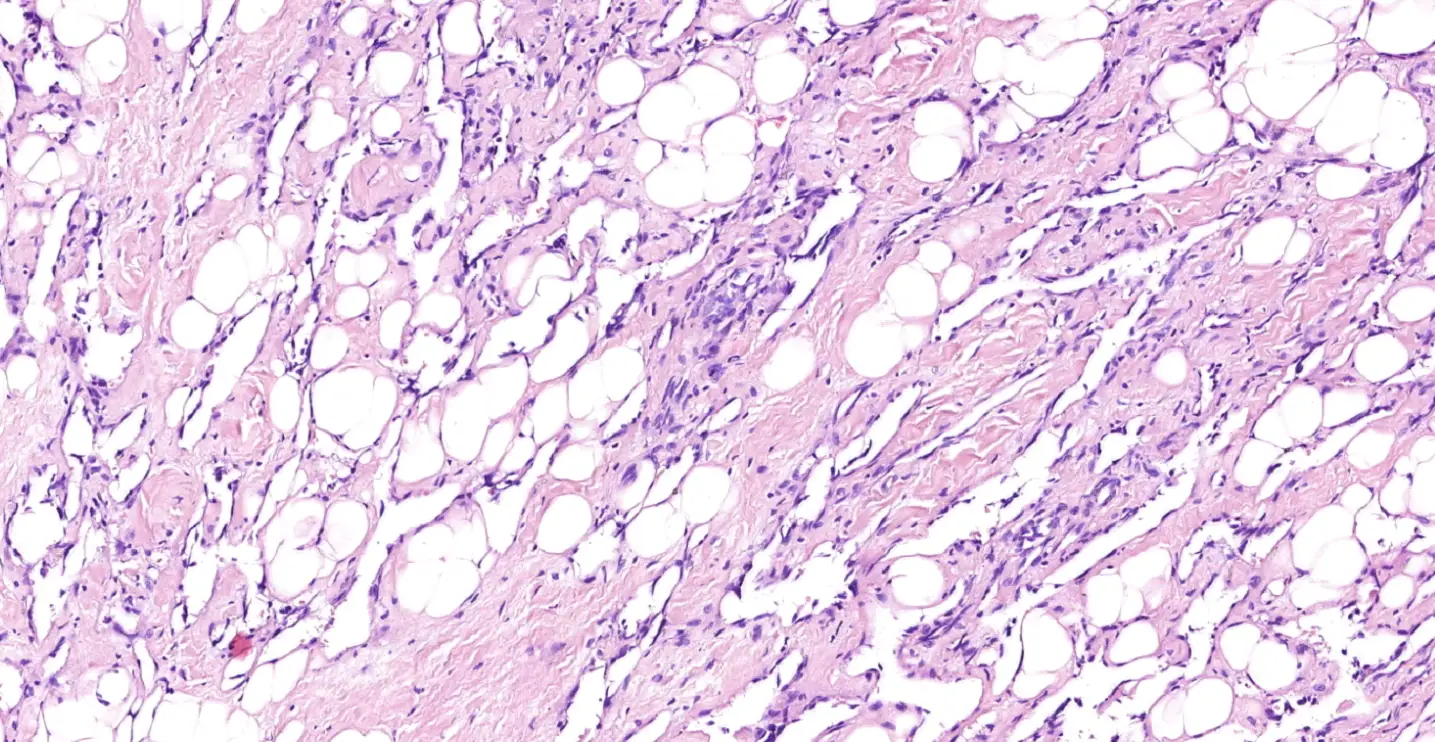

При микроскопическом исследовании ткань железы представлена многочисленными анастомозирующими щелевидными полостями, диффузно инфильтрирующими железистую и жировую ткань молочной железы. Полости выстланы несколько уплощенным эндотелием, ядра эндотелиальных клеток гиперхромные, фигуры митозов в них единичны. Признаков формирования папиллярных выпячиваний эндотелия в просвет сосудов, формирования солидных участков опухоли не определялось. Опухолевые сосуды определяются в интралобулярной строме, что является важным моментом в диагностике первичных ангиосарком молочной железы.

Рис. 1. Просветы сосудов имеют вытянутую, сдавленную или узловатую форму. Сосуды диффузно расположены в паренхиме молочной железы.

Рис.2 Сеть разветвленных тонкостенных сосудов, анастомозирующих между собой.

Рис. 3. Стрелками отмечены просветы опухолевых сосудов. Эндотелиальные клетки уплощены, ядра незаметны, можно обнаружить клетки с гиперхромными ядрами, ядерная атипия минимальна.